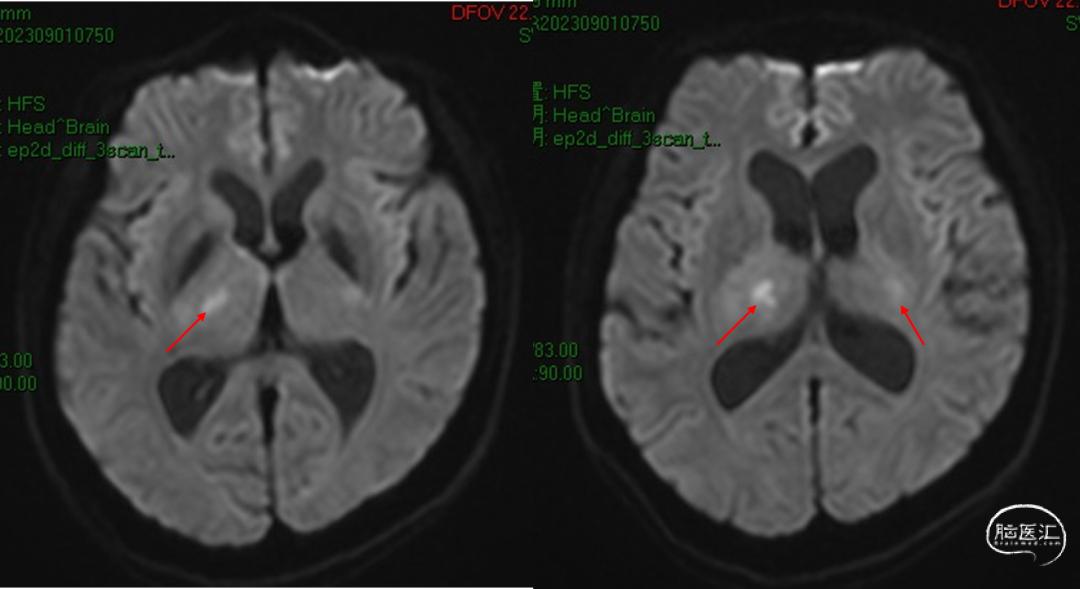

2023-09-01

术后MR未见该中央新发支梗塞

后交通动脉在向后稍内行走的过程中发出两组约2 -8条(以4条为多见)细小的中央支(图1)。前组供应丘脑下部、丘脑腹侧部;视束前部和内囊后肢。后组主要供应丘脑底核。这些中央支之间虽然存在吻合,但其中一支阻塞后,因有效的侧支循环难以建立,故多产生相应供应区的梗死。该病例栓塞假性动脉瘤所在中央支没有症状,考虑为假性动脉瘤导致该中央支缺血耐受和血管代偿。